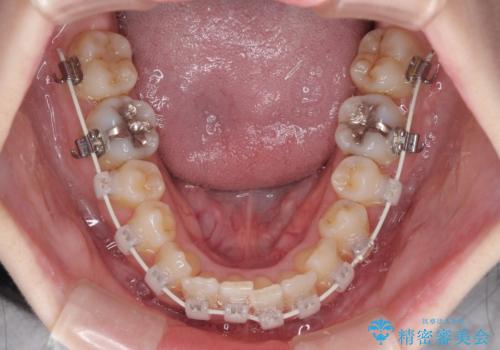

短期間での治療 急速拡大装置を併用したワイヤー装置による矯正治療

- 急速拡大装置・審美装置

急速拡大装置により上顎骨を側方に拡大し、ワイヤー装置により歯列を整えることとしました。

左右ともに奥歯の咬み合わせには大きな問題がなく、窮屈な歯列を解決すれば歯列を整えることできたため、僅か1年で終えることができました。